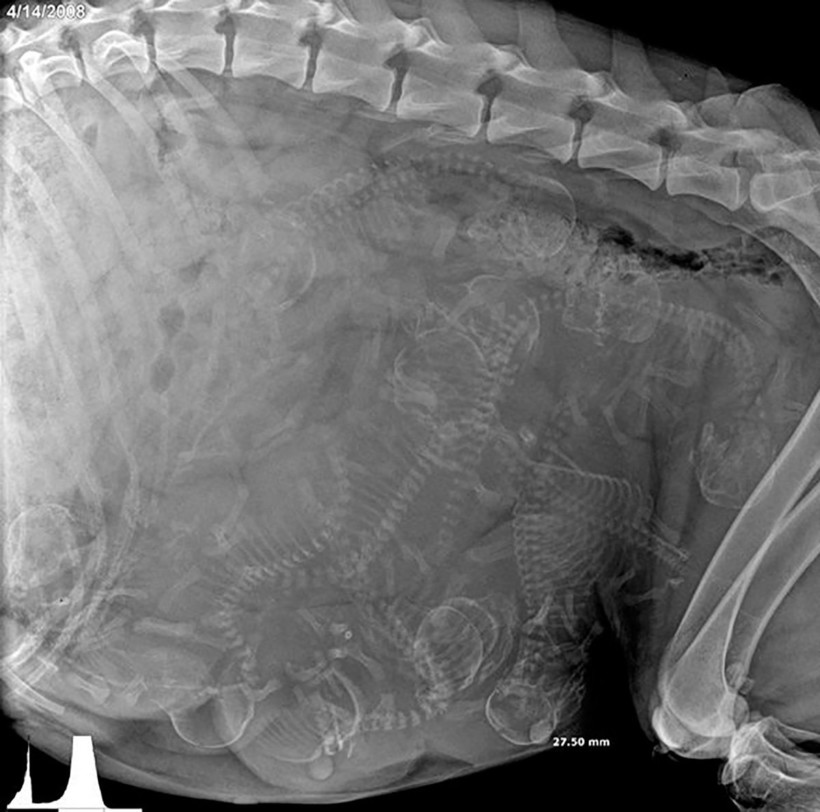

Собака и ее многочисленное будущее потомство